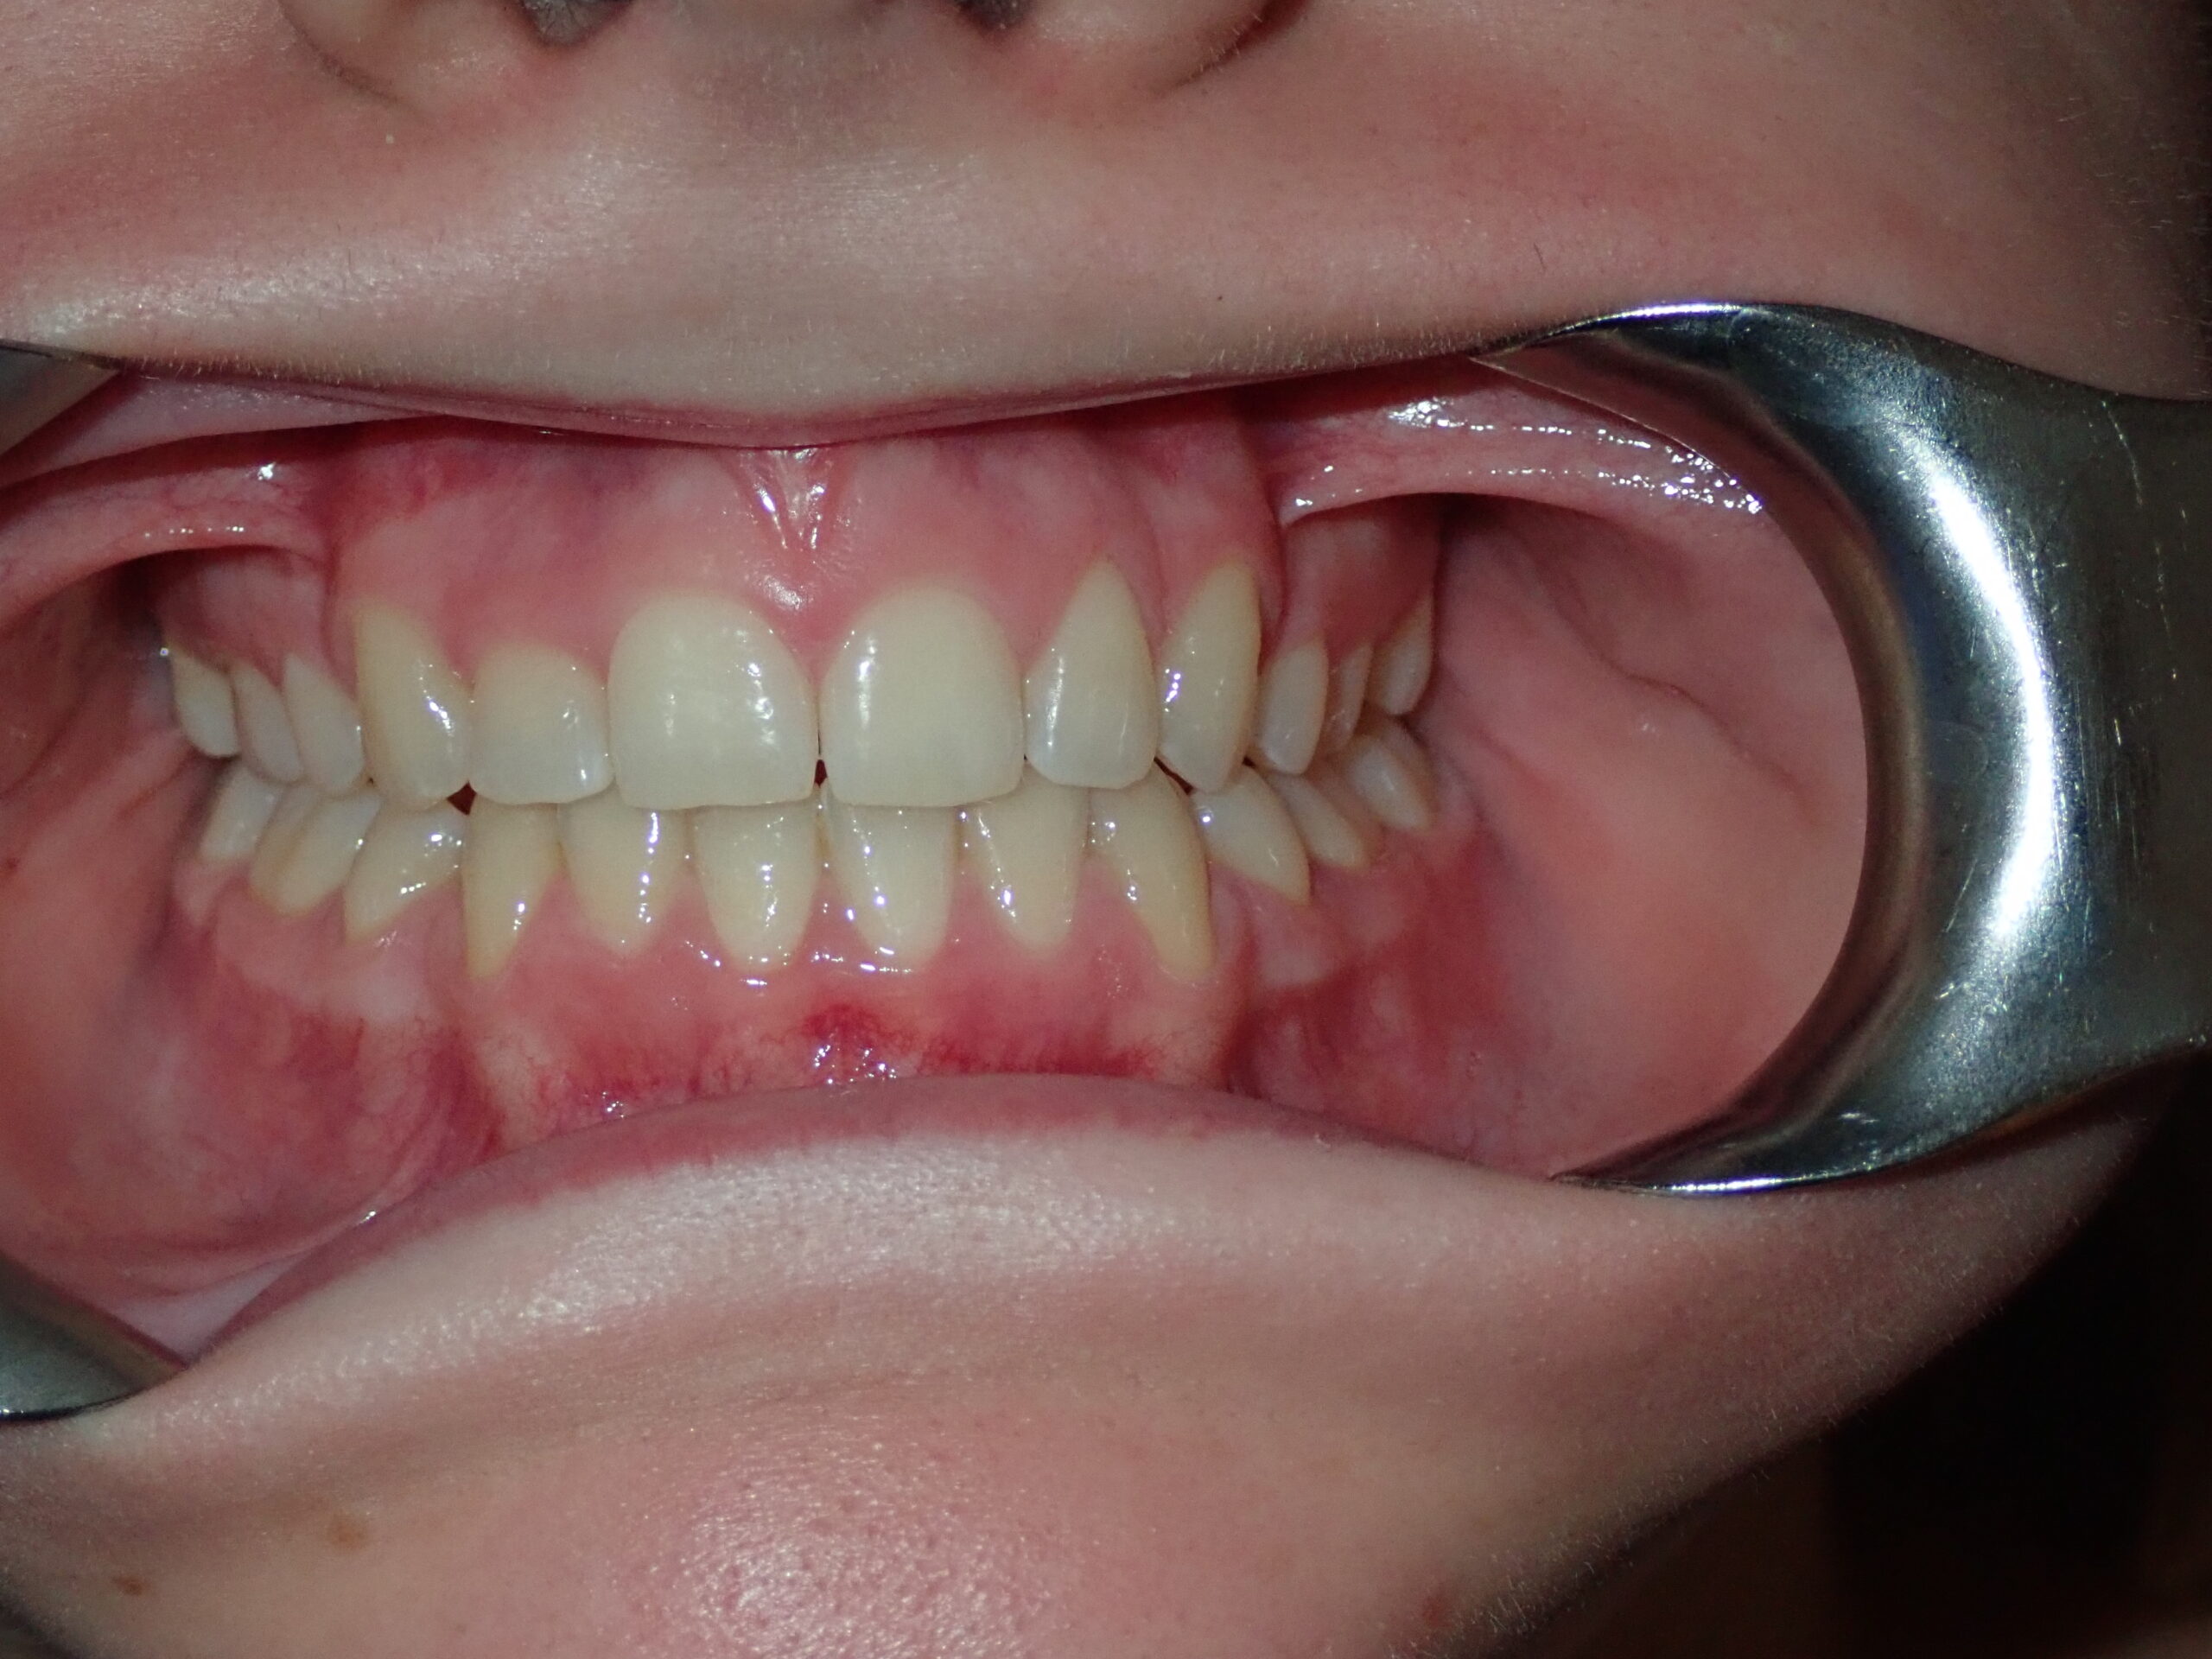

Patient Resultsنتائج المرضى

Real Results. Real Patients.نتائج حقيقية. مرضى حقيقيون.

Airway-centred orthodontics aligns teeth while expanding jaw structure — creating a broader smile, better breathing, and lasting facial harmony without surgery.تقويم الأسنان المتمحور حول الهوائي يُقوّم الأسنان مع توسيع بنية الفك — ابتسامة أوسع وتنفس أفضل وانسجام وجهي دائم بدون جراحة.